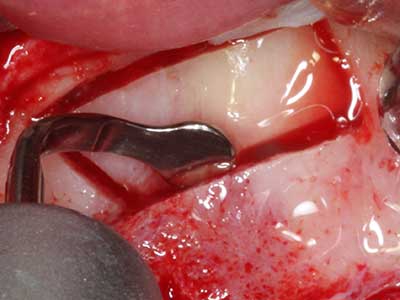

Indication: Apical resection

When surgical procedures are performed on bone in the immediate vicinity of sensitive structures such as blood vessels or nerves, rotary instruments pose a significant risk of iatrogenic injury. Piezoelectric devices can be helpful for preparation of bone covers and removal of hard tissue close to nerves, particularly for exposure of nerves after iatrogenic injury but also during nerve lateralization for resective and reconstructive procedures or implant placement (Fig. 17-20). Light contact between the piezotip and the nerve does not generally result in damage but proceeding incautiously with saw-like motions or attachments where a residual bone substrate remains may cause temporary or even permanent nerve damage. However, the risk of damage is considered to be substantially lower than when using saws or milling instruments (Pereira, Gealh et al. 2014).